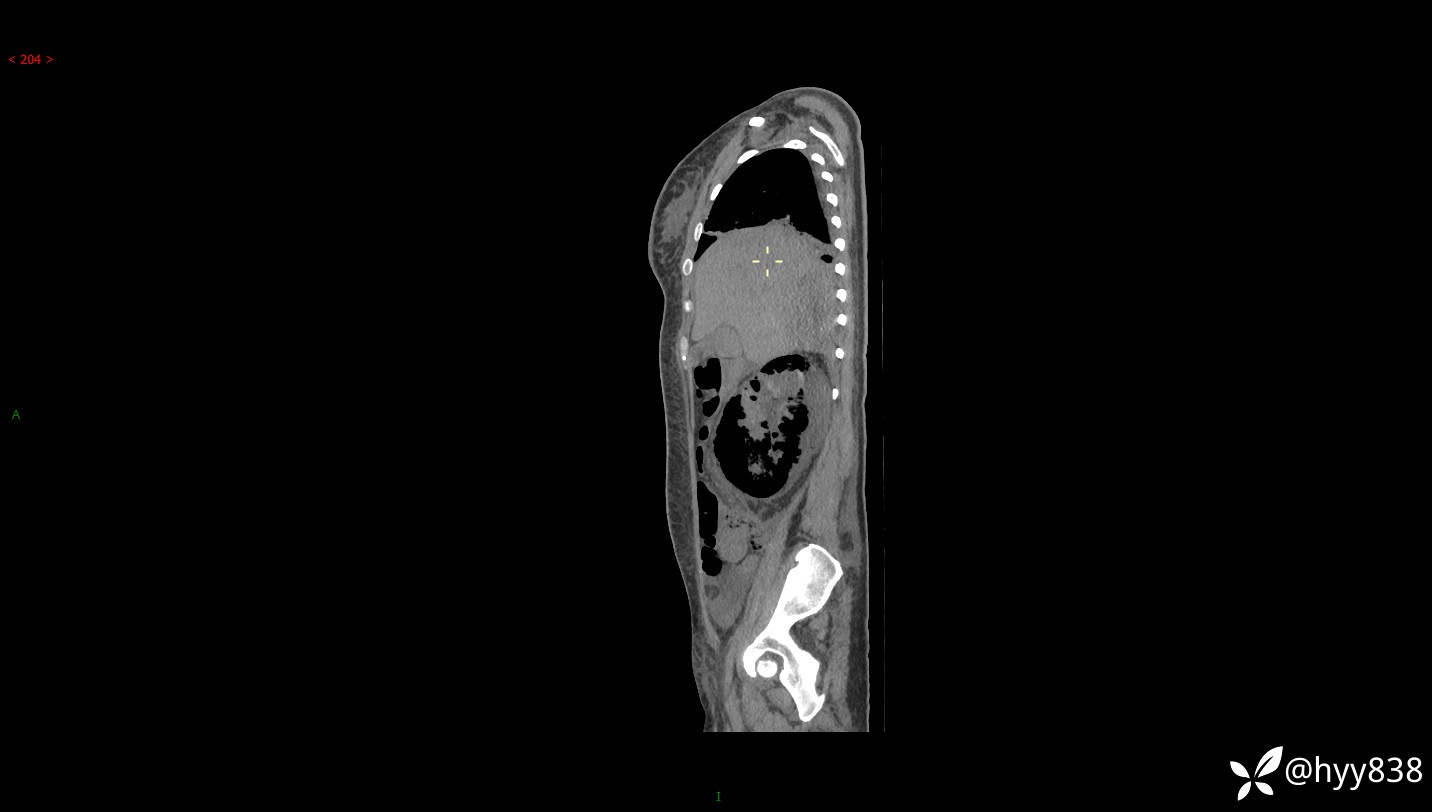

大年三十︱年轻女性,饮酒后突发腰痛,很意外---结果公布~

患者年龄:29岁

主诉:右侧腰部疼痛2天

简要病史:患者2天前和朋友聚餐饮酒时出现右侧腰部疼痛不适,呈间断性胀痛,伴发热、呕吐,无头晕、心慌、胸闷等不适,不伴有尿频、尿急、尿痛等症,院外与当地诊所输液对症治疗症状未见明显改善,今来我院急诊就诊全腹部CT自阅片考虑右肾周围炎,现患者为寻求进一步就诊,来我科就诊,我科以“右肾周围炎”收治入院。 起病以来,患者精神、饮食、睡眠可,大小便正常,体力体重无明显减轻。

临床诊断:肾周围炎

讨论:病变性质?

肾脏CT平扫